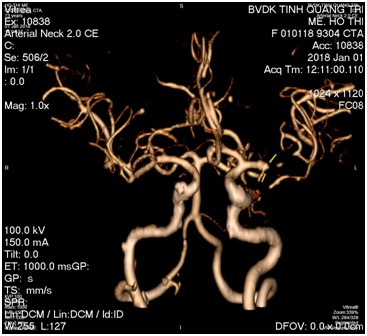

- B/N được điều trị tiêu sợi huyết và chụp MSCT mạch máu não: Kết quả tắc hoàn toàn M2 trái.

Hình: ĐM não giữa trái trước và sau lấy huyết khối